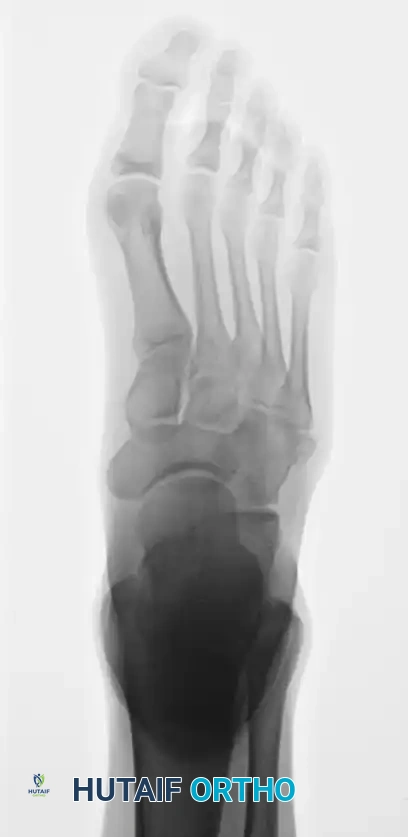

A standard three-view radiographic series of the foot is mandatory for accurate zone classification.

Oblique radiograph, which is often the most sensitive view for identifying non-displaced Zone II and Zone III fractures, as it profiles the fourth and fifth intermetatarsal articulation.